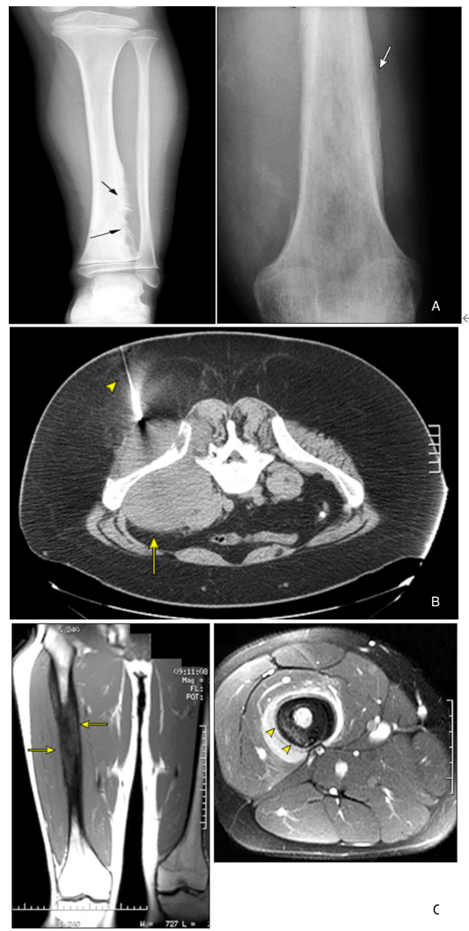

图1:A:尤文肉瘤典型X线表现(左图:左侧胫骨远端尤文肉瘤;右图:尤文肉瘤典型“洋葱皮”样表现);B:巨大骨盆尤文肉瘤CT引导下穿刺,箭头处可见穿刺针;C:尤文肉瘤典型MRI表现(左图,右侧股骨的T1加权冠状位MRI图像显示整个股骨中部被肿瘤广泛破坏(箭头处);右图,通过股骨近端的T1加权轴向MRI图像,相对于周围组织,肿瘤出现高信号(箭头))

图片来源:https://www.cn-healthcare.com/articlewm/20221231/content-1492008.html